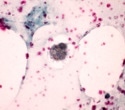

In this study, two types of motor function tests were performed on Parkinson’s disease model mice who were orally fed antioxidants for one week before being given rotenone. Rotenone reduced motor function, but it was recovered in the end. There was also an improvement in intestinal motor function and colon mucosa structure, the unique tissue covering the colon.

Furthermore, cellular experiments utilizing Parkinson’s disease model cells confirmed the biochemical interaction underlying Ecklonia cava’s preventative activity.